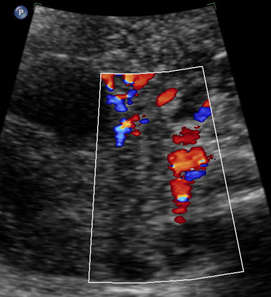

Above. Ovarian cyst. Case 1. 35 weeks gestation. The cystic structure arises in the lower abdomen and is adjacent to the anterior abdominal wall just to the left of mid-line. The cyst measures 45 mm x 36 mm meeting critical cutoff values which increase the risk for torsion and/or infarction.

Above. Ovarian cyst. Case 1. 35 weeks gestation. Blood flow to the cyst is confirmed.